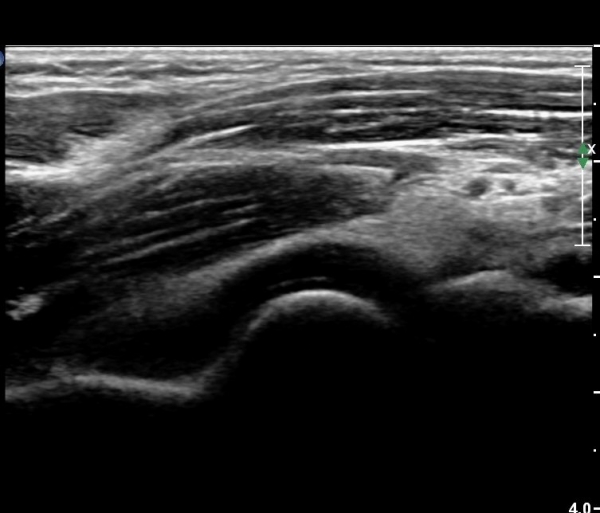

ÆÈ²ÞÄ¡ ¾ÕÂÊ ¿ÜÃø, ¼ÒµÎ(capitulum) Á¾´Ü¸é°Ë»ç¿¡¼­ ¼ÒµÎ Àü¸éºÎ¿Í ¿ä°ñµÎ Àü¸é¿¡ ¼ö¾×Àú·ù°¡ °üÂûµÊ(»çÁø 3, 4).

¼ÒµÎ Ⱦ´Ü¸é°Ë»ç¿¡¼­µµ ¼ÒµÎ Àü¸é¿¡ ¼ö¾×Àú·ù°¡ °üÂûµÊ(»çÁø 5).